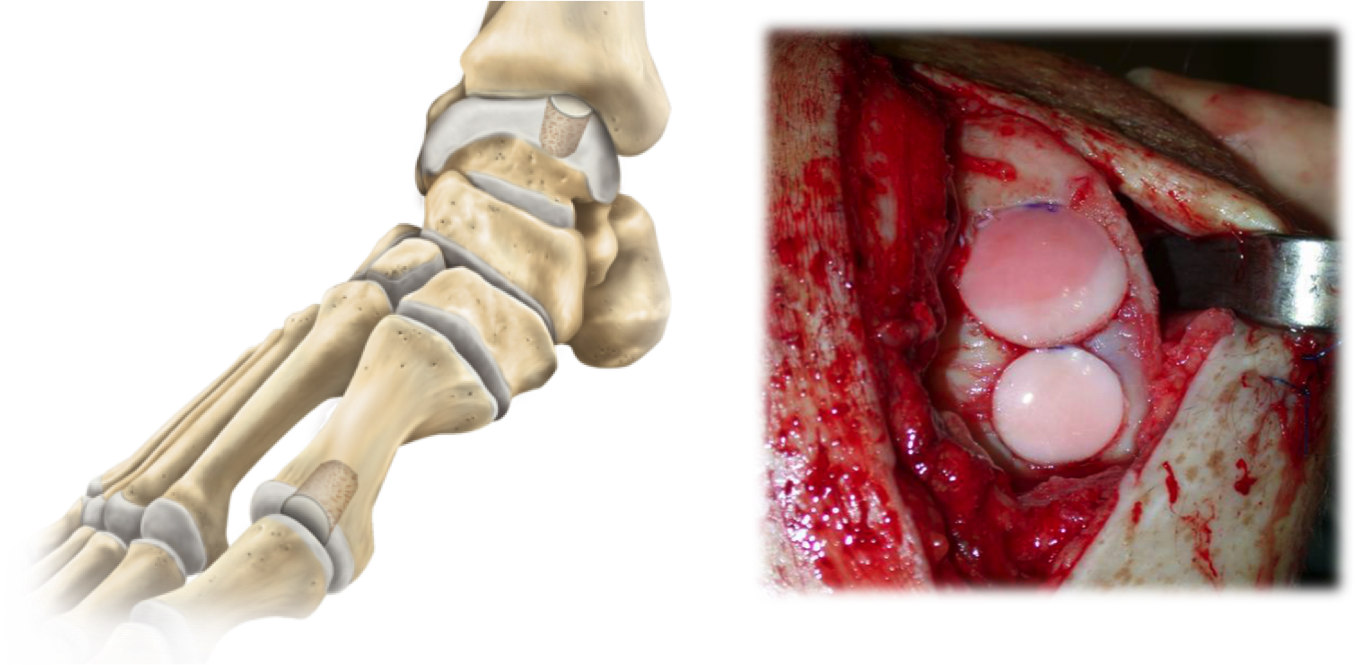

In more severe cases of injuries to the cartilage on the ankle joint we perform something called an OATS procedure where we take cartilage from the knee joint or even a cadaver cartilage plug and place it into a predrilled patient ankle to replace the injury with new cartilage. It works well in the right cases! you can see pic below of the talus bone with circular grafts in place.